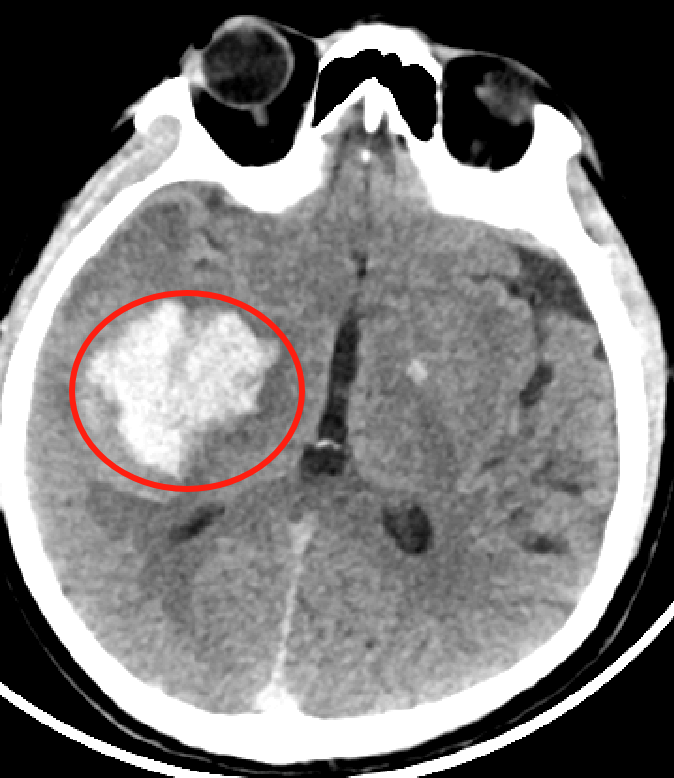

CT影像下可见脑部明显血肿

王大叔抵达我院时,急诊绿色通道已经开启。放射科迅速完成头颅CT,显示“右侧基底节区脑出血,出血量约40ml”。神经外科、急诊科、麻醉科专家同步到位,制定血肿清除手术方案。